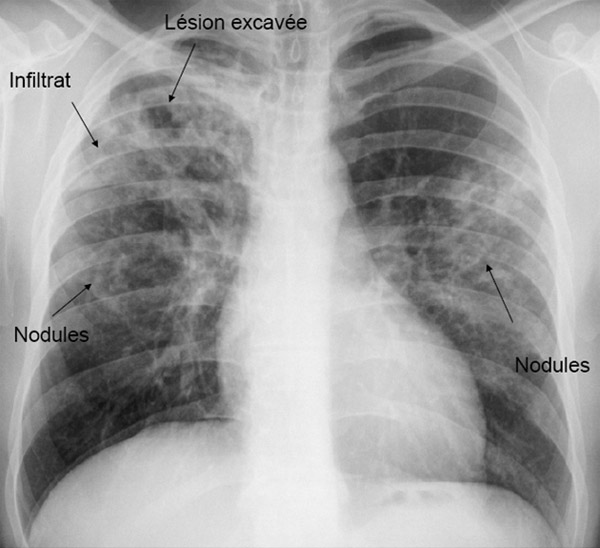

Cette carte de concepts créée avec IHMC CmapTools traite de: Diagnostic, Tuberculose urinaire on peut observer Cystite Hématurie microscopique Leucocyturie aseptique, m.Tuberculosis utilisation de glycérol (LOEWENSTEIN-JENSEN), Volailles On peut observer Aspergillose, tuberculose miliaire on observe lésions anciennes caséeuses et tubercules gris, test à l'interféron gamma est rapide, Primo-infection stabilisée on observe tubercules caséeux arrondis, jaunâtres de quelques mm Noeuds lymphatiques caséeux, Intradermotuberculinisation chez Homme, Nécropsique chez Bovins, Bovins si Généralisation précoce lente, Tuberculose extra-pulmonaire comme Tuberculose génitale, Aspergillose avec pseudo-tubercules jaunes caséeux lésions exclusivement pulmonaires, Prélevements de liquide pleural, Nécropsique si suspicion de TB prélevement des noeuds lymphatiques et des organes, tuberculose pulmonaire on peut observer signes cutanés, Intradermotuberculinisation grâce à des tuberculines, 3 mois si négatif, signes fonctionnels et généraux comme fièvre, Bovins si Primo-infection stabilisée, Hématoxyline-Eosine montrent Cellules de Langerhans, Tuberculose extra-pulmonaire comme Tuberculose cutanée